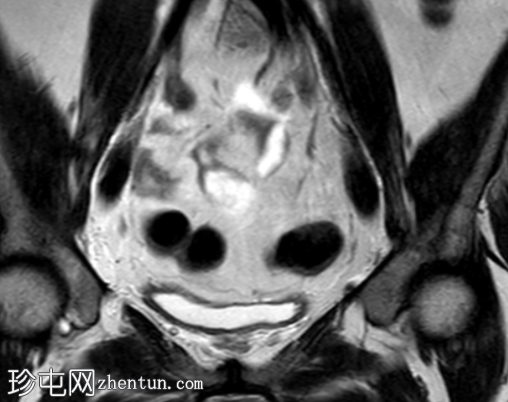

轴位T1加权像

脂肪抑制像

盆腔MRI显示左侧骶前区有两个小囊性病变,位于左侧附件的预期解剖位置。

病变在T2加权像上呈高信号,边界清晰,囊壁轻度增厚,光滑。在T1加权脂肪抑制像上,一个病变内部呈高信号,另一个病变呈低信号。静脉注射对比剂后,可见轻度周边囊壁强化,未见强化的实性成分。

未见扩散受限。病灶与邻近盆腔血管关系密切,无周围炎症改变、盆腔淋巴结肿大或游离液体的证据。